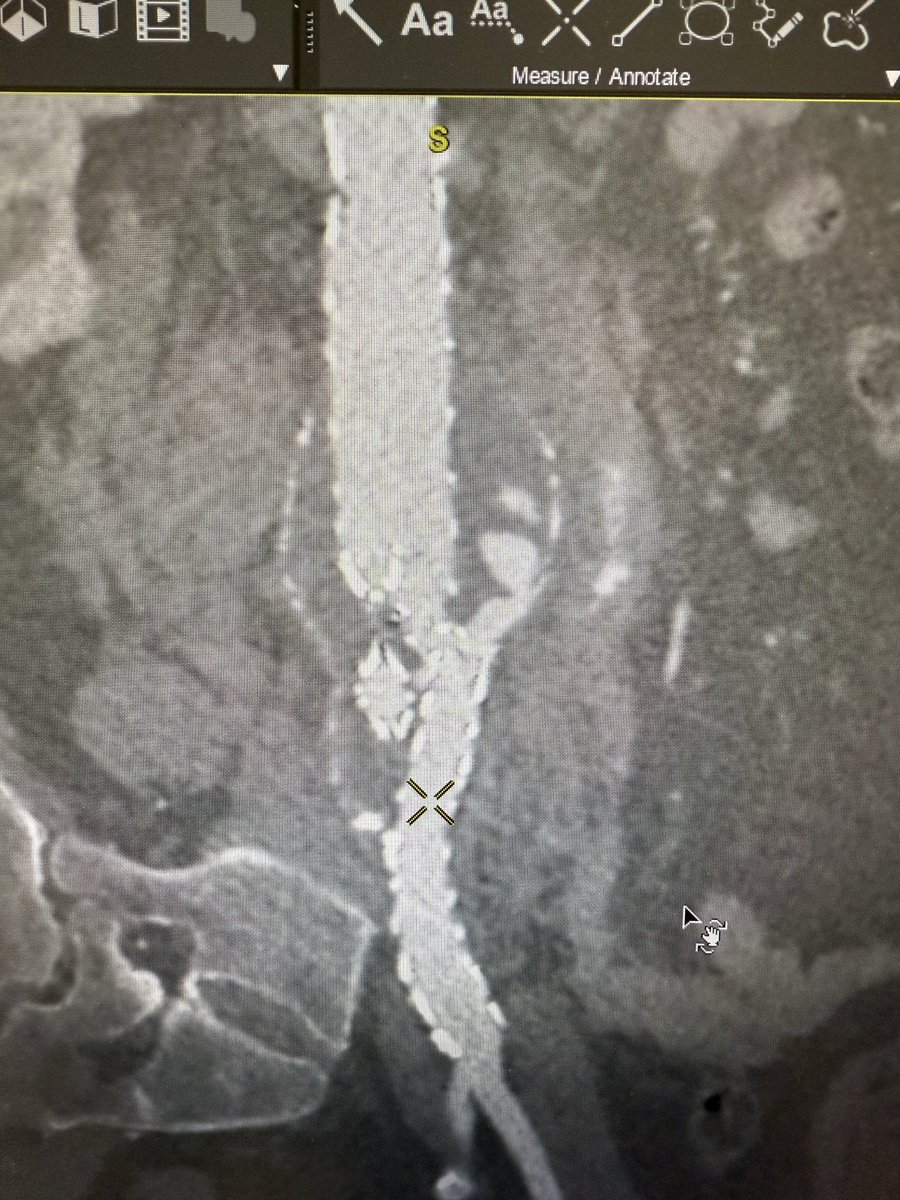

Diagnosis : Popliteal artery entrapment syndrome causing acute limb ischemia Intra-op pictures

#vasctwitter 17 yrs old male, keen football player.sudden onset pain in right leg and foot. Absent foot pulses and pale foot. CTA below. What is the diagnosis? Look at cross sectional image?! How would you treat?